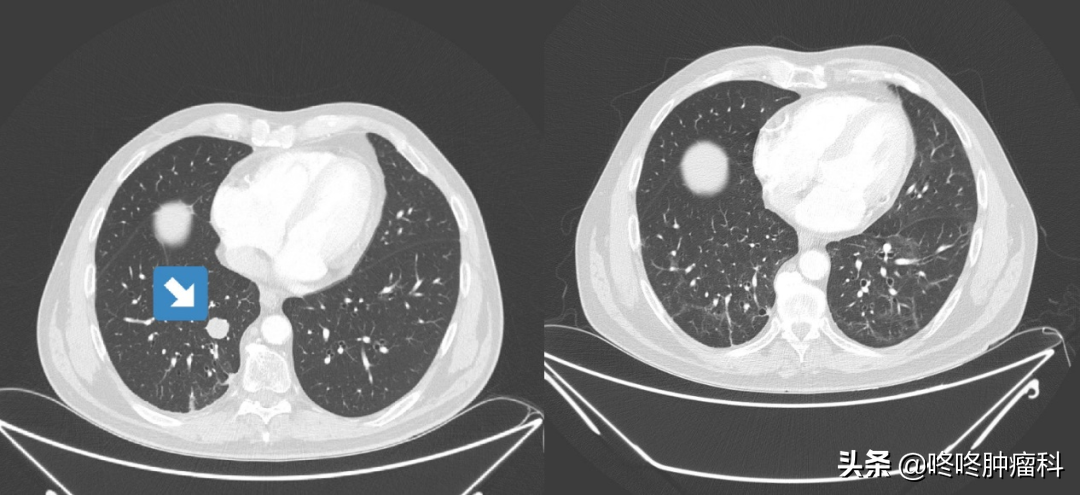

患者肺中的腫瘤(左圖箭頭處)在新冠肺炎感染后(右圖)完全消失

雖然這位患者同期還在使用PD-1抑制劑Nivolumab,但在相關試驗中,使用Nivolumab的27位IV期肺鱗癌患者中,只有一人獲得了完全緩解[1]。這位患者的完全緩解,很有可能是和新冠病毒感染有關的。